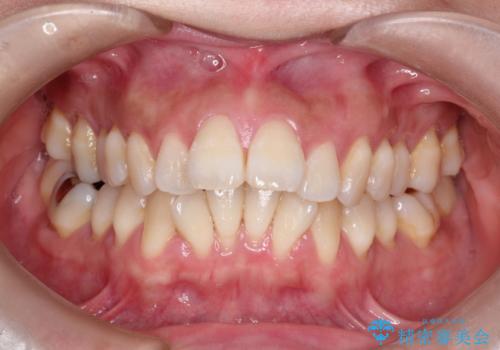

出っ歯で口が閉じずらい ワイヤー抜歯矯正

- 治療期間

- 2年1ヶ月

- 出っ歯がきになるとのことで来院されました。

上顎の前歯は前方に傾斜しており、下あごの前歯にもガタガタがありました。

上下左右の小臼歯を合計4本抜歯して矯正することとしました。

矯正を開始する前から歯肉退縮があり、悪化しないように注意しながら矯正治療を行いました。